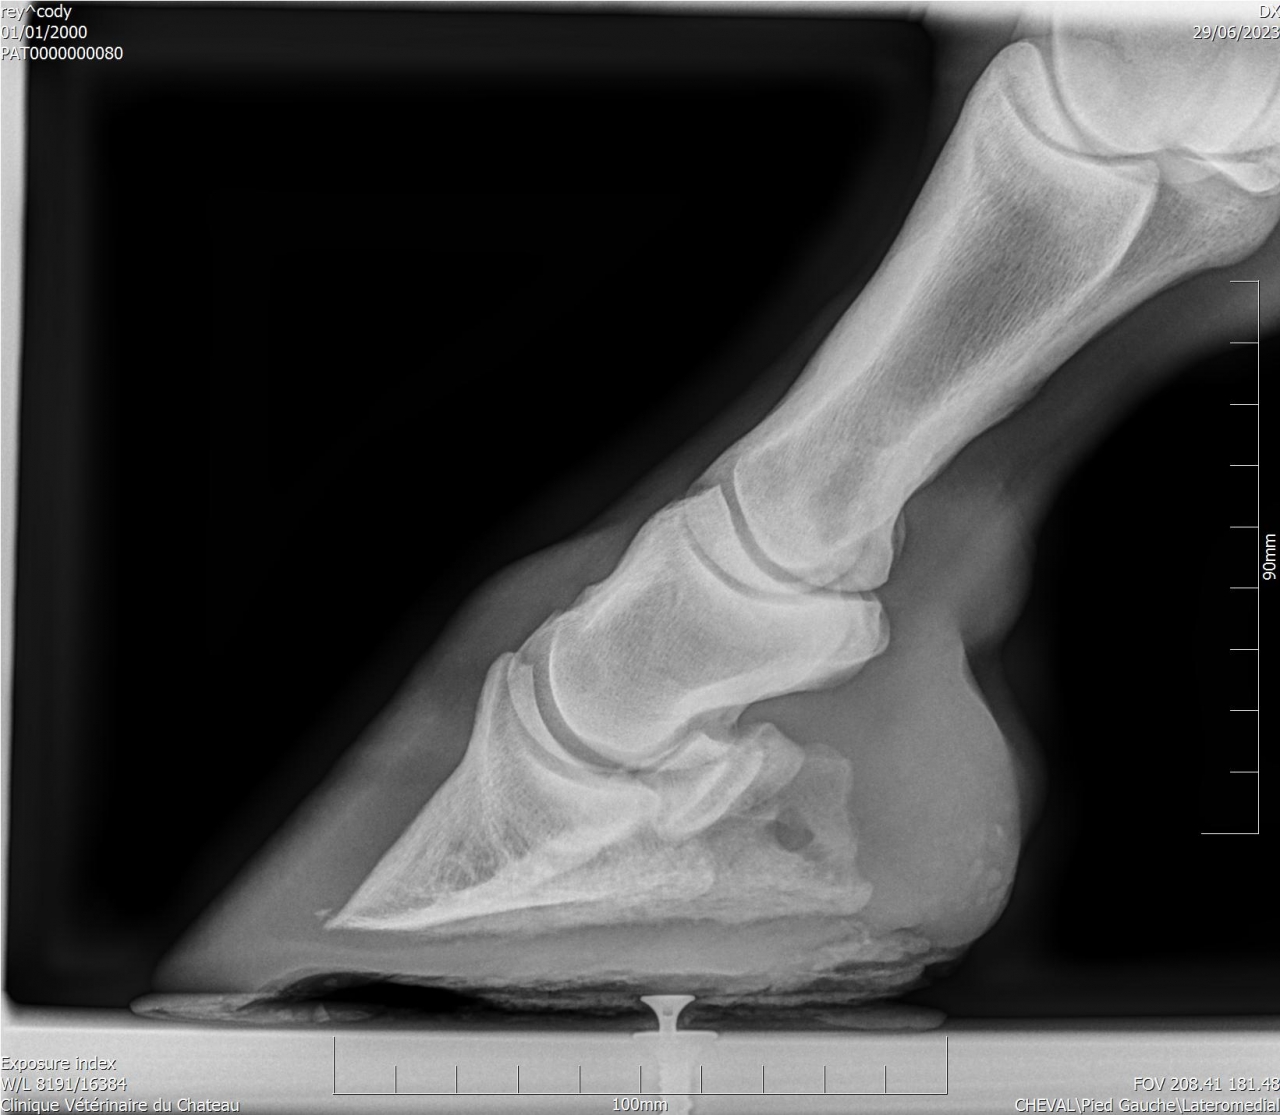

| Dire merci | Cody a une sensibilité que personne n'arrive à expliquer ... Les radios montrent une ossification des processus palmaires sur les 2 antérieurs, et une légère bascule de P3 sur l'antérieur gauche. A priori le naviculaire est correct. J'ai trouvé un maréchal-ferrant qui pose des Duplos. Vaut il mieux brocher ou coller ? |

| Dire merci | Deux personnes m'ont parlé des Duplo, les vétos ont conseillé ferrure en M ou ferrure normale ... L'année dernière Cody a été ferré avec des fers oignons et plaques en cuir, ça n'a rien changé. Ces fers ont été conseillés par le maréchal-ferrant car le véto consulté à l'époque conseillait des egg bar. Il me semble qu'avec l'ossification des processus palmaires les fers en métal n'étaient pas l'idéal. Voici les radios : ![]() ![]() ![]() ![]() J'essaye de régler les problèmes physiques pour voir si ça change quelque chose monté. Je commence par les pieds. |